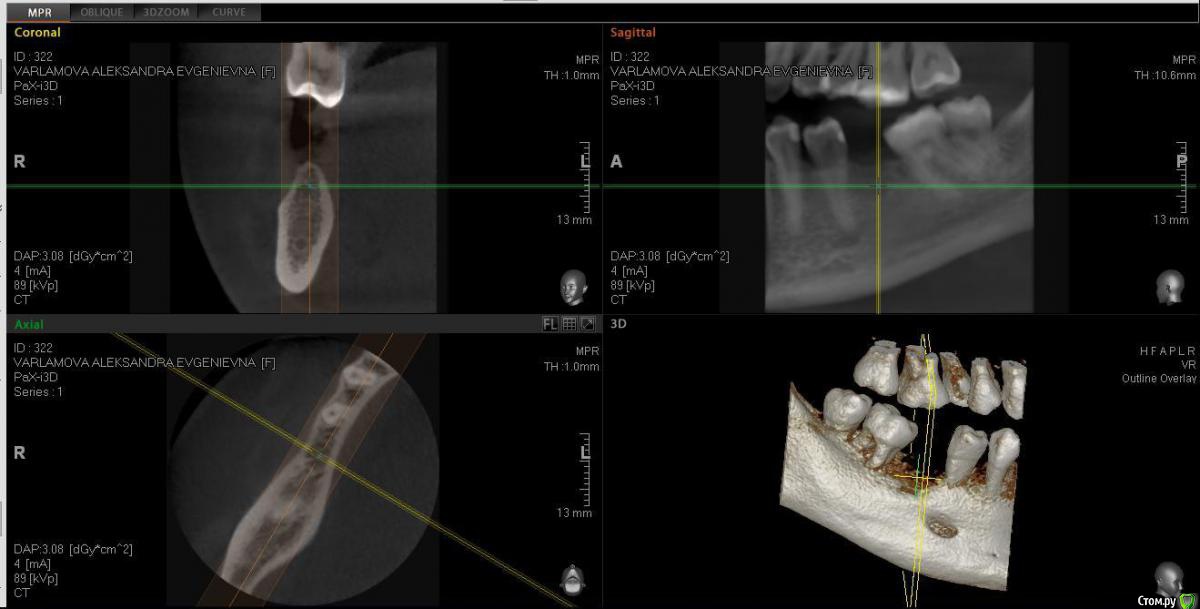

Александра_85 Опубликовано 12 марта, 2015 Поделиться Опубликовано 12 марта, 2015 (изменено) Здравствуйте, собираюсь сделать имплантацию 6 нижнего зуба справа.Удален этот зуб был 4 года назад, кость довольно сильно ушла.Мой имплантолог советует кость не наращивать, и установить тонкий импрант АльфаБио.Хотелось бы услышать ваше мнение.Во вложении ортопантограмма годичной давности, и свежее КТ по ссылкеhttp://www.fayloobmennik.net/4686662 Я не очень понимаю, как выложить срез.Сделала скрин, может по нему будет понятно Изменено 12 марта, 2015 пользователем Александра_85 Ссылка на комментарий

Александра_85 Опубликовано 12 марта, 2015 Автор Поделиться Опубликовано 12 марта, 2015 да, пожалуйста, ждем снимокВот. Ссылка на комментарий

red_butler Опубликовано 12 марта, 2015 Поделиться Опубликовано 12 марта, 2015 (изменено) Вот.я бы имплантировал с одномоментной костной пластикой, однако существует современная тенденция - ставить импланты малого диаметра и ограничиваться пластикой десны Изменено 12 марта, 2015 пользователем red_butler 1 Ссылка на комментарий